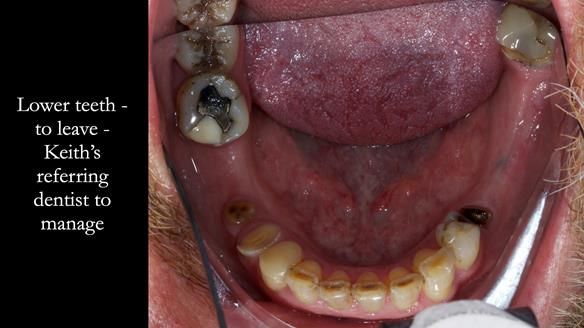

Keith’s case was one of the most challenging and rewarding cases I’ve treated this year. This 64 year old man presented with ill-fitting acrylic partial dentures that lacked stability, retention, and aesthetics. They constantly broke. He had lost the upper front teeth in a road traffic accident in his early 20s. The unopposed teeth had erupted, taking up space. After careful planning, we made a durable, metal-based upper partial denture/splint to address his dental concerns. He loved the outcome.

2. Onlay preparations: Composite onlays were fitted for his upper left premolars to repair these teeth and support the new denture.

I also used the Dahl concept to re-establish the occlusion upon fitting the RPD, which helped to intrude the lower left canine without needing to grind it too much.